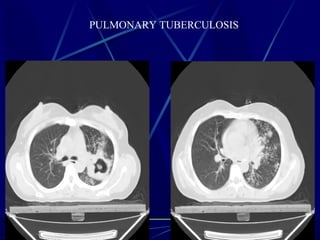

PULMONARY TUBERCULOSIS

Typical Tree-in-bud appearance in a patient with active TB.

Tree-in-bud

Tree-in-bud describes the appearance of an irregular and often nodular

branching structure, most easily identified in the lung periphery.